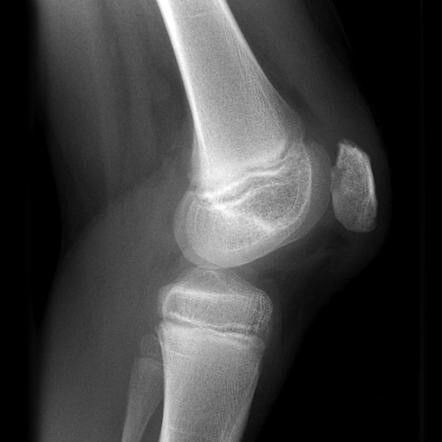

آرتروز

آرتروز زانو یک بیماری شایع است. تقریبا ۳۳ درصد از افراد بالای ۶۵ سال با آرتروز زانو درگیر می باشند. این یک بیماری مخرب مفصلی است که با عوارضی مانند: از بین رفتن غضروف زانو، رشد بیش از حد استخوان در قسمت لبه آن ( زائده استخوانی) ، افزایش تراکم بافت استخوان ( سفت شدن در محل غضروف) مشخص می شود.